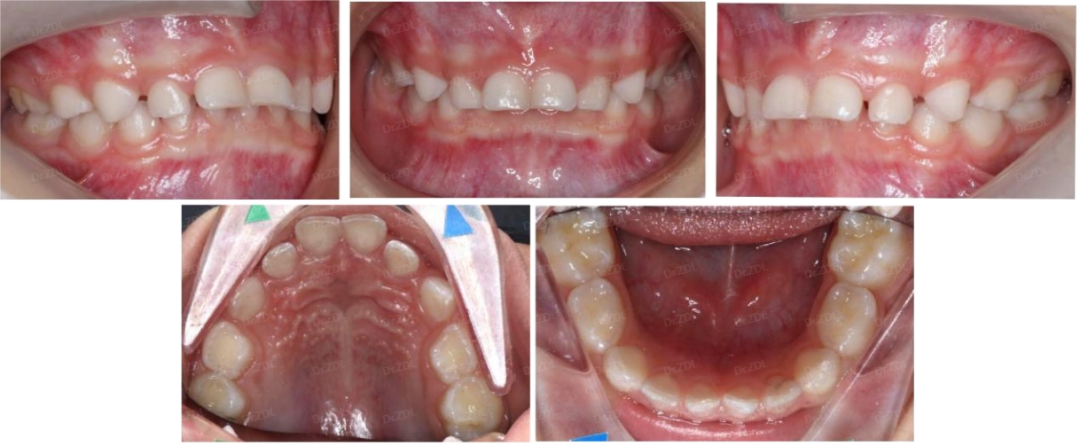

Grace硅胶牙套案例3:

这位小朋友,主诉牙凸、牙不齐、没下巴,临床检查看上前牙III度深覆合深覆盖,骨性II类倾向,上颌牙弓狭窄,鼻唇角偏大、颏唇沟比较深。

根据孩子牙齿情况,采用Grace轨道式硅胶矫治器,恢复上下颌正常牙弓宽度,匹配上下颌牙弓形态,引导上下恒牙正常萌出,引导下颌前伸,并日常辅助唇肌功能训练。

佩戴 Grace10 个月,上下颌牙齿排齐良好,咬合打开良好,深覆合深覆盖得到改善,侧貌形态良好。

佩戴 Grace24 个月,上颌内收,下颌前伸,上下颌乳牙完全替换完成,牙弓形态正常,牙齿排齐良好,前牙正常覆合覆盖。